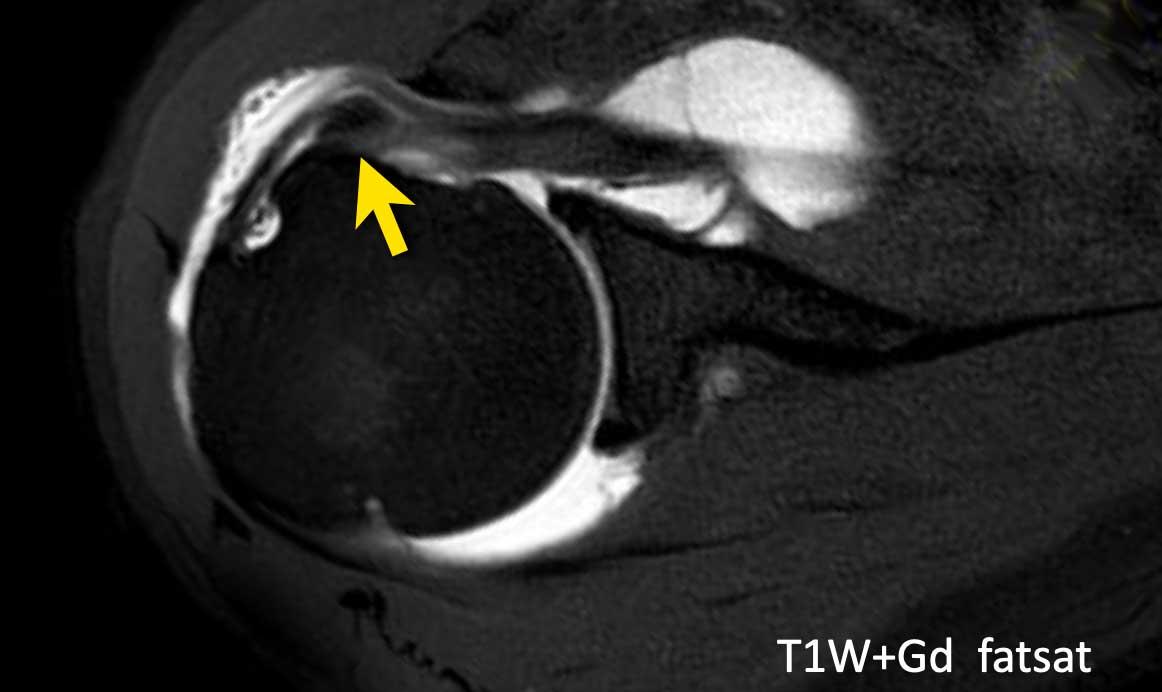

Chụp cộng hưởng từ khớp với hình ảnh trục T1 có ức chế mỡ: Gân cơ nhị đầu bị di lệch về phía trong gân cơ dưới vai, như được chỉ ra bởi mũi tên.